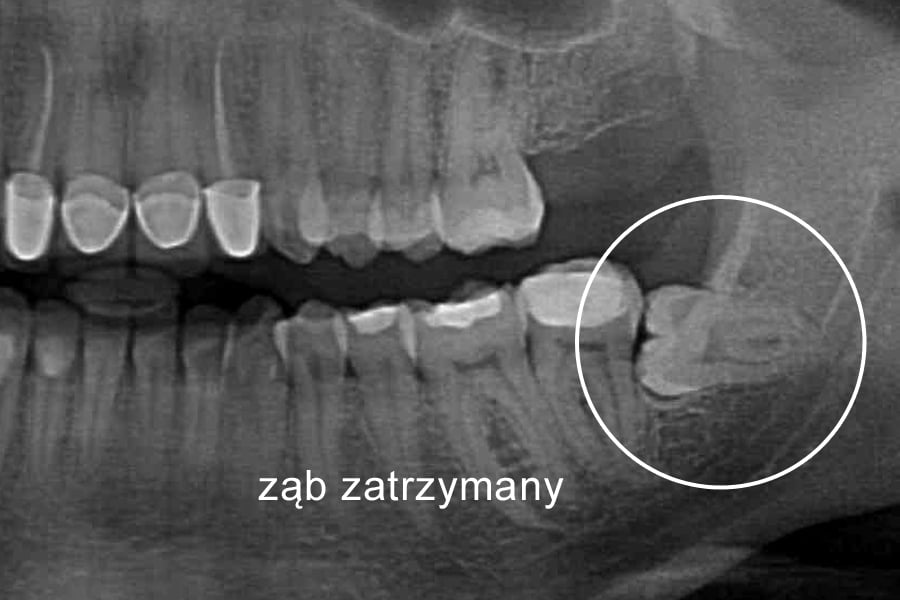

Ząb zatrzymany to w pełni wykształcony ząb stały, który po okresie fizjologicznego wyrzynania pozostaje w utkaniu kostnym szczęk lub żuchwy. Może być on zatrzymany całkowicie, gdy jest otoczony kością ze wszystkich stron lub zatrzymany częściowo, gdy ma koronę poza kością pokrytą jedynie dziąsłem.

Rozpoznanie zęba zatrzymanego opiera się na badaniu rentgenowskim.